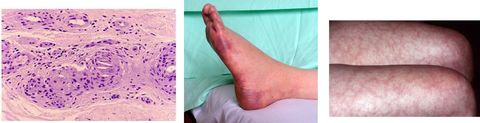

CRIOGLOBULINEMIA

EMBOLOS POR COLESTEROL